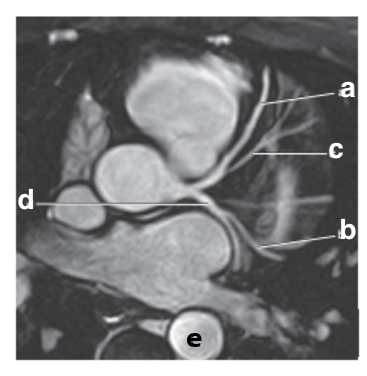

Which letter is the Pulmonary trunk ?

d

What is letter b ?

Left ventricle

Which letter is the superior vena cava ?

What is letter a ?

Left atrium

Right ventricle

What is letter d ?

Pulmonary trunk

Bicuspid valve / LT AV valve